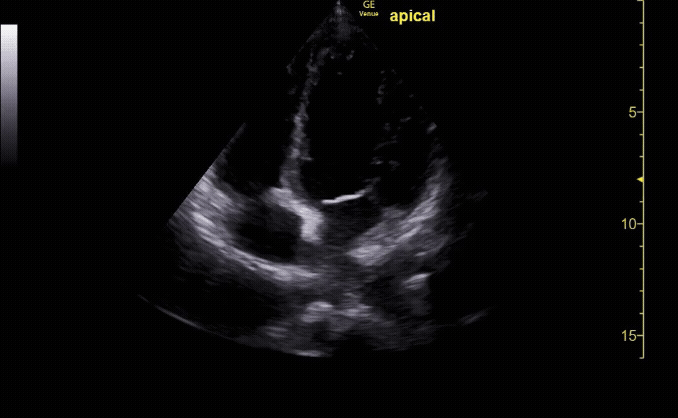

Subxiphoid view showing the liver, right ventricle, right atrium, left atrium, and left ventricle.

c/o Kyle Ackerman, MD